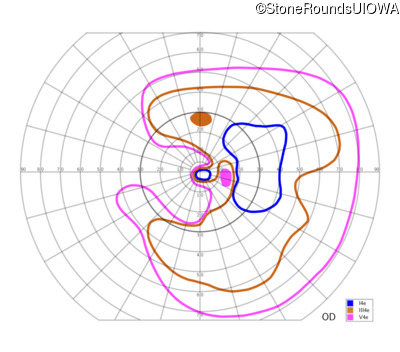

This 81 year old man began using a flashlight to read menus in his 40's. At age 75 his ophthalmologist noticed abnormal fundus findings and referred him to a retina specialist.

| OD | OS | ||

|---|---|---|---|

| Late Onset Retinal Dystrophy | C1QTNF5 | Ser163Arg AGC>AGA | AD |